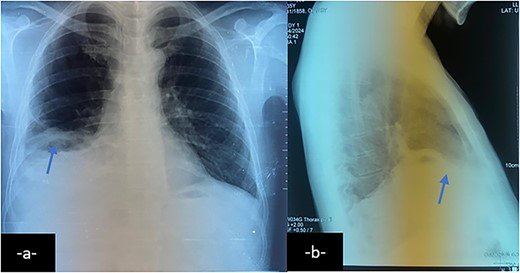

Upon further examination, the patient’s blood tests showed elevated inflammatory markers, and imaging studies revealed atelectasis in the right lower lung lobe, pleural effusion, and a subphrenic collection (Fig. 2). A computed tomography (CT) scan confirmed the presence of an intrahepatic collection communicating with the pleural cavity, indicating a potential BBF (Fig. 3) which was confirmed on magnetic resonance imaging (MRI) (Fig. 4). A drain was inserted under CT guidance (Fig. 5), and an endoscopic retrograde cholangiopancreatography (ERCP) revealed spontaneous bile leakage from the duodenal bulb. A stent was placed to drain the biloma (Fig. 6). Surgical intervention was avoided due to the patient’s liver condition.

Chest X-ray on postero-anterior (a) and lateral views shows right basal atelectasis of the lung, right pleural effusion and sub phrenic collection with air-fluid level (arrow).

Chest X-ray may reveal dense opacities in the right lower lobe.